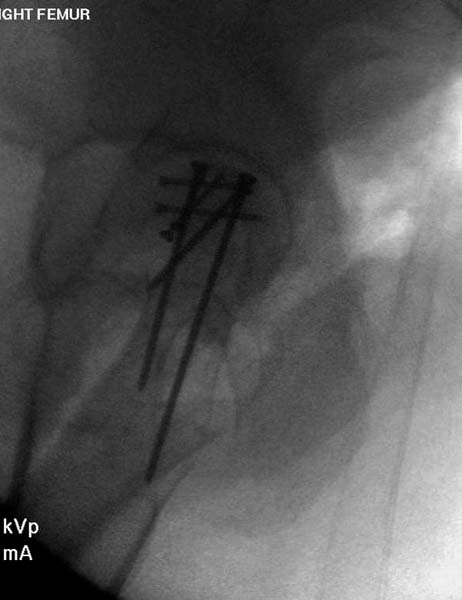

2) Стержневой АНФ на 4-6 стержнях на диафиз правого бедра;

Учитывая тяжесть травмы, пациентка скорее всего попадает под DCO. Ночью стабилизировать бедро стержневым аппаратом, вывих попробовать вправить, зафиксировать гипсом или аппаратом (в зависимости от состояния кожных покровов. Таз стабилизировать простынею. Перевод в реанимацию. По стабилизации, состояния: открытое вправление, внутренняя фиксация перелома головки, тарана, АВФ на таз, штифтование бедра (последнее - можно еще отложить)

Остеосинтез бедра не стали делать из-за множественных переломов ребер с ушибом грудной клетки и поэтом у закончили фиксацию бедра наружным фиксатором.

Около 11.00 вечера больная переведена в реанимацию, без сознания, но стабильная.. На третьий день провели стабилизацию перелома бедра антеградным остеосинтезом.

Закрытый БИОС решает множественные проблемы связанные с лечением переломов, но проблема дистальной блокировки без рентгена до сих пор остается нерешенной. Рекламированные производителями приспособления для дистальной блокировки из-за различной кривизны кости не эффективны или стоит очень дорого (Smith&Nephew SureLock). Задержка операции из-за блокировки не всегда удовлетворяет, и многих вынуждает искать альтернативные методы фиксации. С результатами таких действий, остеомиелитом и несращениями, встречаемся в ежедневной жизни..

Для решения проблемы дистальной блокировки компания DigiMed недавно предложила систему блокировки без рентгена. Пока в стране только два набора и только для антеградных гвоздей, но компания работает над созданием устроиства для других гвоздей тоже..

Результат первых случаев показала отсутствие разницы между занятиями на муляжах, а также Workshop и с удивительной точностью вывел латерально над кожей специальное сверло. Дальше по сверлу тонкий направитель и проводится сверление каннюлированным сверлом....